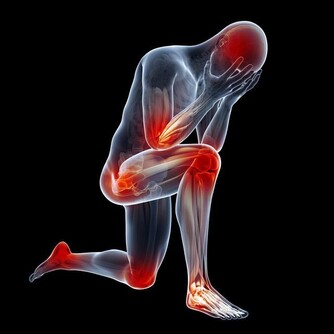

荷爾蒙失調的十大徵兆

調養身體,最怕「頭痛醫頭,腳痛醫腳」,無法針對病因做根本性的調理,往往只起到緩解病徵的作用。

常見的各種健康問題,諸如失眠、肥胖、腸胃失控等,

皆與人體的「荷爾蒙」失調息息相關,更易并發自體免疫疾病,影響全身性機能。

根據健康媒體《StepToHealth》指出,以下是最常見的十種「荷爾蒙失調」癥狀: